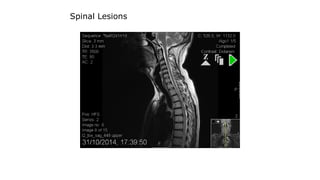

Spinal Lesions

cord lesion